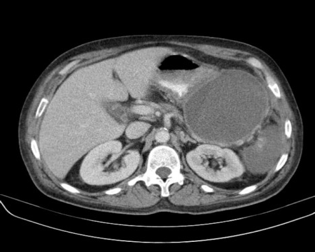

La clasificación revisada de Atlanta para la pancreatitis aguda distingue entre las colecciones de líquido y la necrosis pancreática según su temporalidad y características. Las colecciones de líquido y necrosis pueden ser agudas, es decir, ocurrir dentro de las primeras 4 semanas del inicio de la enfermedad, o crónicas, si persisten más allá de este período. Además, estas colecciones pueden ser estériles o infectadas. Las colecciones crónicas, como los pseudocistos y la necrosis encapsulada, se caracterizan por la formación de una cápsula que limita la expansión del proceso inflamatorio y facilita la diferenciación de las áreas afectadas. En el caso de las colecciones agudas, la necrosis pancreática puede extenderse rápidamente y convertirse en una complicación grave.

Entre el 5 y el 10% de los pacientes con pancreatitis aguda pueden experimentar complicaciones derivadas de necrosis pancreática infectada, lo cual constituye una de las principales causas de mortalidad en esta enfermedad. La necrosis pancreática puede complicarse con infecciones secundarias, que a menudo se desarrollan debido a la presencia de tejidos necrosados susceptibles a la colonización por microorganismos, especialmente aquellos de origen entérico. La presencia de necrosis infectada se asocia con síntomas sistémicos de gravedad, como fiebre, leucocitosis, y en algunos casos, shock. Además, la necrosis pancreática infectada está estrechamente vinculada con el fallo de varios órganos, tales como el sistema gastrointestinal (por ejemplo, hemorragias gastrointestinales), el sistema respiratorio (insuficiencia respiratoria) y el sistema renal (insuficiencia renal aguda). En aproximadamente el 50% de los casos, la necrosis pancreática infectada es responsable del fallo multiorgánico, lo que contribuye a la alta mortalidad de esta condición.

El tratamiento de la necrosis pancreática infectada requiere una intervención agresiva, que a menudo incluye la desbridación quirúrgica del tejido necrosado para eliminar la fuente de la infección. Dado que la necrosis pancreática infectada es una de las principales causas de mortalidad en la pancreatitis aguda grave, el diagnóstico temprano y preciso de esta complicación es crucial. La aspiración con aguja fina guiada por tomografía computarizada (TC) de las áreas de necrosis pancreática es un procedimiento clave para obtener muestras de tejido que permitan la identificación de microorganismos responsables mediante la tinción de Gram y cultivos microbiológicos. Este procedimiento debe realizarse de manera repetida si es necesario, ya que la infección puede ser difícil de detectar inicialmente debido a la ubicación de las áreas afectadas y la variabilidad de los síntomas.

Los pseudoquistes son colecciones encapsuladas de líquido que contienen una concentración elevada de amilasa, una enzima pancreática, y son una complicación común en la evolución de la pancreatitis aguda, especialmente cuando se utiliza la tomografía computarizada (TC) para monitorear el curso de la enfermedad. Estos pseudoquistes suelen formarse después de un episodio de pancreatitis aguda, como resultado de la ruptura de los conductos pancreáticos o la fuga de jugos pancreáticos hacia los tejidos circundantes. Aunque inicialmente no contienen un epitelio verdadero, se desarrolla una cápsula fibrosa que los encapsula, lo que los diferencia de otras colecciones de líquido. Esta cápsula puede ser visible en las imágenes de TC, lo que permite la identificación de los pseudoquistes como colecciones bien delimitadas.